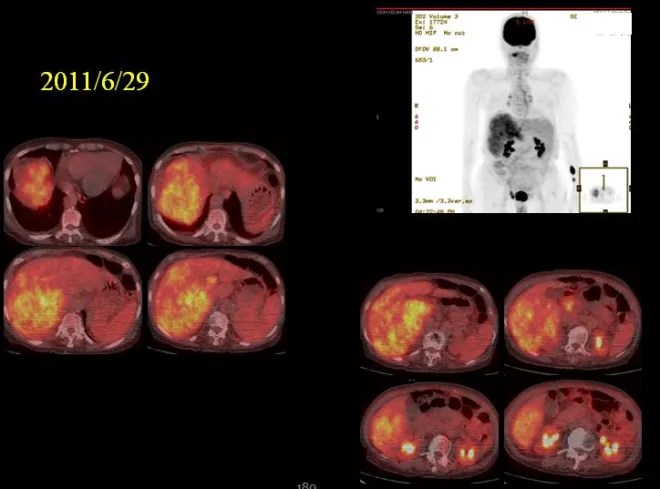

As seen on the PET scan, the entire right hepatic lobe was involved by tumor. I therefore explained my perspective to the family. If the patient were younger, I would consider attempting treatment, and some prolongation of survival might be expected. However, given the current condition—with both pleural effusion and ascites requiring albumin supplementation, and the likelihood of repeated hospital visits for paracentesis and supportive care—it would place a significant burden on both the patient and the family. In today’s busy circumstances, this can be especially difficult, and in such an elderly patient, I explained that a more conservative, comfort-oriented approach might ultimately be more appropriate.

The patient was able to tolerate the course well for nearly two years, with both ascites and pleural effusion resolving, allowing a return to normal daily activities. The CT scan obtained 19 months later showed the findings as above.